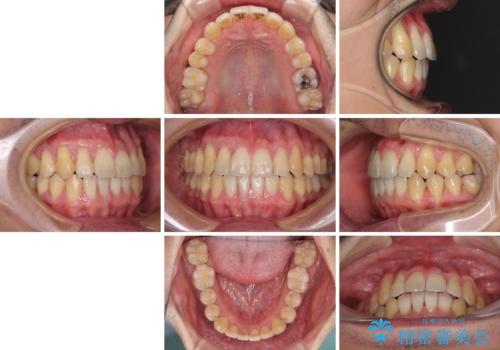

インビザラインによる反対咬合の改善は、上の歯が下の歯を乗り越えていく期間に咬み合わせが非常に不安定となり、治療が長期化することがあります。

また、ワイヤー矯正と異なり歯軸改善の強い力を前歯にかけるため、反対咬合で裏側にある歯の歯肉が退縮しやすくなります。

矯正治療により元々気になっていた八重歯と、反対咬合が改善された歯の2本に対して根面被覆を行い、審美面の改善も達成しました。